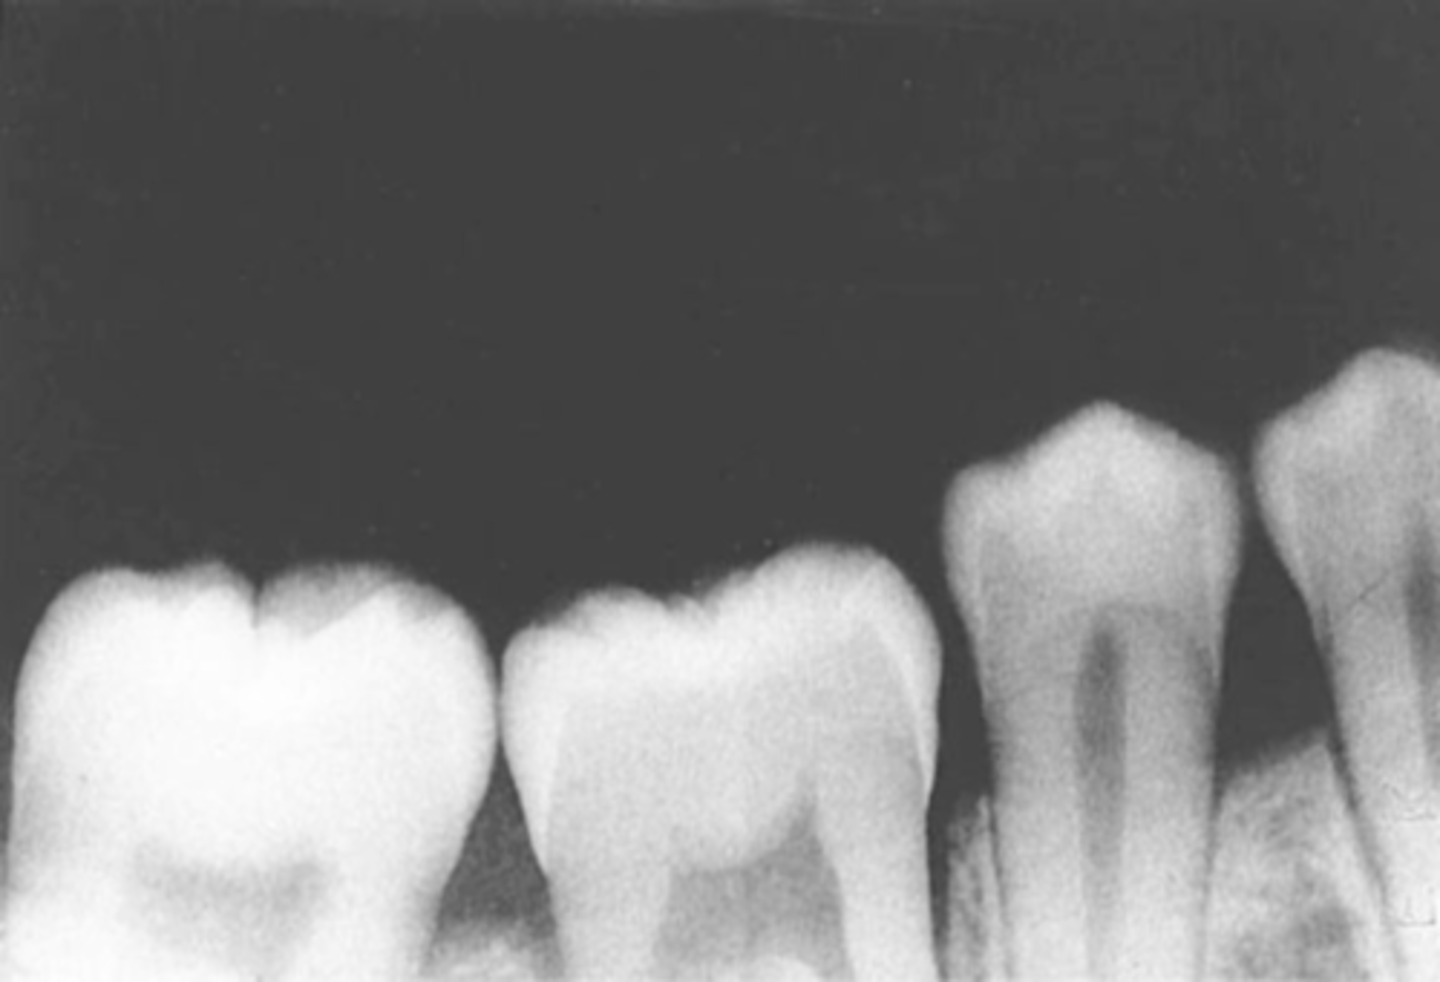

absence of apical structures

receptor not positioned to cover apical region of teeth

bite block not placed on the teeth being exposed